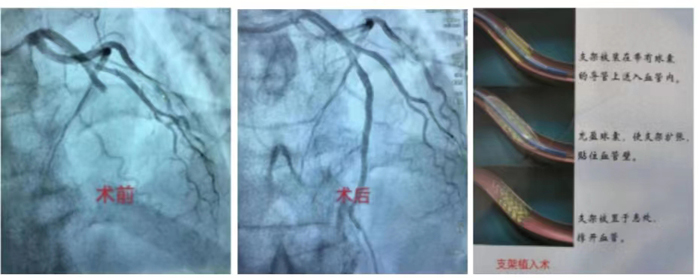

冠心病介入診療技術(shù):科室常規(guī)開展冠狀動(dòng)脈造影術(shù)、經(jīng)皮冠狀動(dòng)脈球囊擴(kuò)張術(shù)(PTCA)、經(jīng)皮冠狀動(dòng)脈藥物球囊擴(kuò)張術(shù),振波球囊技術(shù)治療冠脈嚴(yán)重鈣化病變、冠狀動(dòng)脈支架置入術(shù)、心臟血管內(nèi)超聲檢查(IVUS)、血流儲備分?jǐn)?shù)測定(FFR)、冠狀動(dòng)脈旋磨成形術(shù)等介入手術(shù)。在冠脈左主干、分叉病變、慢性完全性堵塞性病變、彌漫性及鈣化病變等復(fù)雜病變方面積累了豐富的經(jīng)驗(yàn)。胸痛中心針對急性心肌梗死患者開通綠色通道,其中急診冠心病介入診療技術(shù)為棗莊地區(qū)開展最早,挽救急性心肌梗死病人最多的科室。

急診PCI術(shù):是指在患者發(fā)生急性心肌梗塞后12小時(shí)內(nèi)進(jìn)行的冠狀動(dòng)脈血運(yùn)重建,患者首先在導(dǎo)管室行冠狀動(dòng)脈造影術(shù),找出冠狀動(dòng)脈“罪犯”血管及其病變部位,對病變部位行經(jīng)皮冠狀動(dòng)脈腔內(nèi)成形術(shù)和植入支架,使閉塞的血管得以再通,梗死相關(guān)心肌得以及早的再灌注和功能恢復(fù)??梢哉f,急診PCI術(shù)為挽救急性心梗垂危的生命在最短的時(shí)間內(nèi)構(gòu)建了一條綠色的通道,提高危重癥患者的搶救成功,使急性心肌梗死的死亡率下降,提高患者的生活質(zhì)量。因此,在急性心肌梗死的時(shí)間窗內(nèi),介入治療已是首選治療手段,其急診PCI大大降低死亡率及心肌梗死并發(fā)癥,提高生存率及改善生活質(zhì)量。